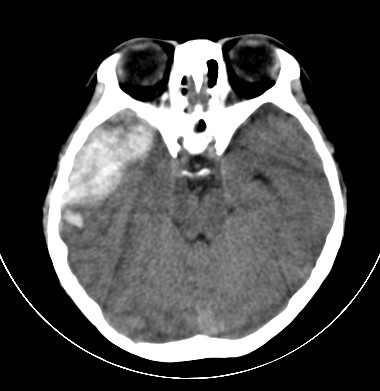

外伤一天,m,21y,骨窗示右颞骨骨折.

请大家看看,是脑内还是脑外(硬膜下还是硬膜外).请说说理由.谢谢.

右侧颞叶大片状形态不规则高密度影,边缘较模糊,无明显白质挤压移位。支持脑错裂伤、脑内血肿。

右侧颞叶大片状形态不规则高密度影,内缘较模糊,外缘紧贴颅板,无明显白质挤压移位伤。

依据:1.右侧颞叶不规则形血肿密度影,周围有水肿;

2.有明显占位效应;

3.颅板下硬膜下间隙存在。

脑内脑外全有,上方比较局限近似梭形改变,考虑硬膜外血肿。没有跨过颅缝,且是脑膜中动脉所在的位置。中线移位,占位效应明显。后方条带状增高影,周围有水肿带,考虑脑内血肿。

右颞叶见混杂密度灶(以高密度灶为主)右侧脑室受压变形,中线结构左移,右颞部颅骨内板下见弧形高密度灶,右侧裂池及部分脑沟内见高密度灶;

结论:1:右颞叶脑挫裂伤;

2:右侧硬膜下血肿;

3:蛛网膜下腔出血。